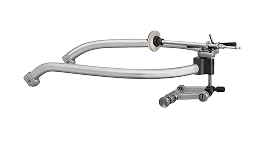

Обследование у врача-гнатолога всегда включает артикуляционный анализ и исследование на диагностических моделях. Это основа, которая позволяет доктору точно спланировать лечение с учетом анатомических и функциональных особенностей пациента. Исследование на артикуляторе предполагает использование особого устройства — лицевой дуги, которая фиксирует положение верхней челюсти относительно основания черепа. Данные с нее передаются в артикулятор — прибор, имитирующий движения челюстей. Он позволяет врачу «вне рта» понять, как двигаются челюсти, какие формируются контакты зубов при смыкании и как работает сустав. Диагностическими моделями называют точные цифровые или восковые (Wax-Up) шаблоны зубов пациента, которые изготавливают в лаборатории по 3D-сканам. С их помощью врач оценивает смыкание зубов, симметричность зубного ряда, выявляет аномалии прикуса, скученность, диастемы, тремы, неправильное положение, повороты отдельных зубов и патологическую стираемость зубной эмали. Кроме того, для лечения патологий из области гнатологии в клинике «Полный Порядок» в СПб мы выполняем: Конусно-лучевую компьютерную томографию (КЛКТ). Исследование позволяет оценить состояние твердых тканей ВНЧС, положение суставных головок в покое и при открывании рта, выявить признаки артроза, травм и разрастания костной ткани — остеофиты. В отличие от обычного рентгена, который дает плоское изображение, КЛКТ показывает все анатомические структуры в объеме и под любым углом. Аксиографию. Это метод диагностики, при котором специальный прибор записывает движения нижней челюсти и суставных головок в режиме реального времени. Он измеряет амплитуду и траекторию движений челюсти, определяет симметричность работы суставов, а также выявляет их функциональные блоки.